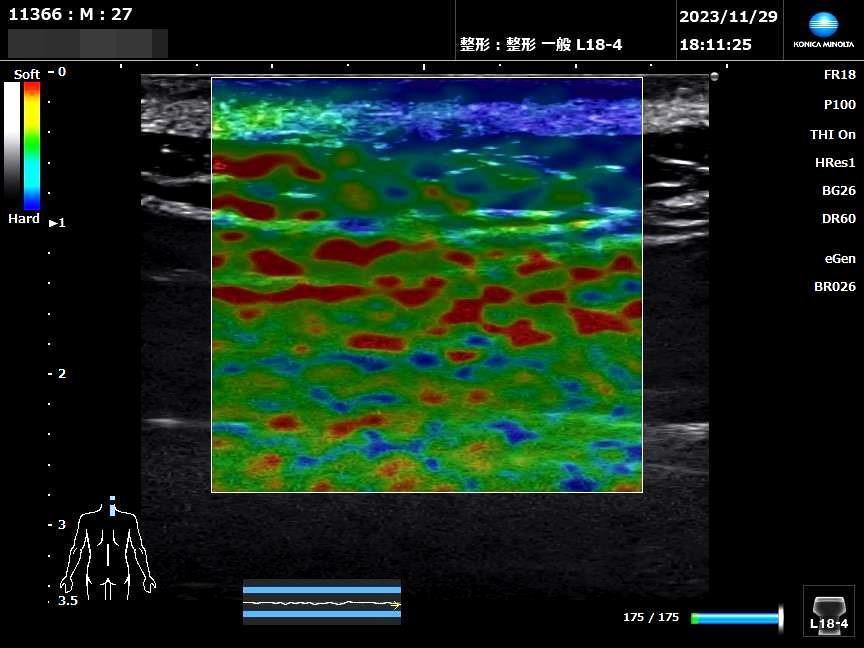

負傷部位の見える化

*エラストグラフィーサンプル画像

七番整骨院で交通事故施術は特に負傷部位の状態を可能な限り客観的に評価し患者様と損保担当者及び提携医療機関と共有できるように超音波エコー観察を行います。

医療機関でのレントゲンやMRI、CT検査以外に超音波エコー観察の手段でエラストグラフィーを用いることで筋腱軟部組織の緊張を客観的に評価することができます。

交通事故によるむち打ち症状は、レントゲンやMRIを撮っても「骨に異常なし」と言われ、痛みの原因がはっきりしないことが少なくありません。しかし、患者様自身は「首や肩がパンパンに張って痛い」という確かな実感を抱えています。この「筋肉の張り(硬さ)」を客観的に捉えるのが、超音波エラストグラフィーです。

1. 「痛みの正体」が色や数値で見える

これまでは、施術者が手で触れて「硬いですね」と判断する(触診)しかありませんでした。エラストグラフィーを使うと、筋肉の硬い部分を色(青色など)や数値(kPa)で画面に映し出せます

メリット: 「自分の首がどれくらい硬くなっているか」を、納得感を持って確認できます。

2. 深い場所にある「しこり」も見逃さない

むち打ちの痛みは、表面だけでなく、指が届かない深い場所の筋肉(深層筋)が原因のこともあります。

メリット: 通常の検査では見つかりにくい深い場所の筋肉のこわばりを特定でき、ピンポイントな治療(筋膜リリースやリハビリ)につなげられます。

3. 治療の効果を「数字」で実感できる

「通院しているけれど、本当に良くなっているの?」という不安に対し、数値で経過を追うことができます。

メリット: 前回の検査より数値が下がっていれば、痛みの軽減と合わせて「組織が柔軟に戻っている」という回復の証拠になります。

4. 体に優しく、その場でわかる

レントゲンのような被曝の心配がなく、何度でも検査が可能です。また、首を動かしながら「どの動きで筋肉が硬くなるか」をリアルタイムで観察できるのも大きな特徴です。